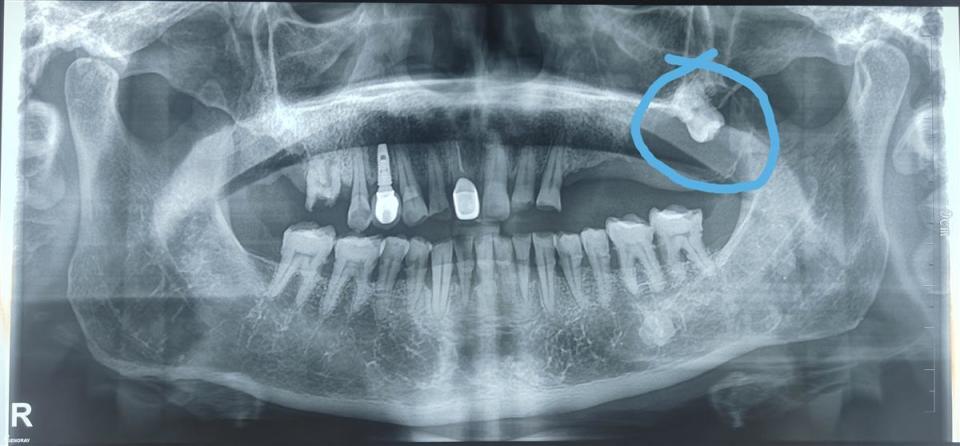

刘爹爹的口腔影像图

“囊肿大约有3cm×4cm×5cm,患者看到片子都难以置信。”据该院口腔医学中心主任向国林介绍,刘爹爹上颌骨囊肿内包裹的牙齿是一颗高位阻生智齿,埋伏在上颌骨内几十年,长期慢性刺激颌骨组织,进而产生病变,逐渐形成囊肿。如果不及时拔除阻生智齿、摘除囊肿,上颌骨骨组织会继续遭到破坏,将导致面部变形、牙齿松动,还可能会继发感染。